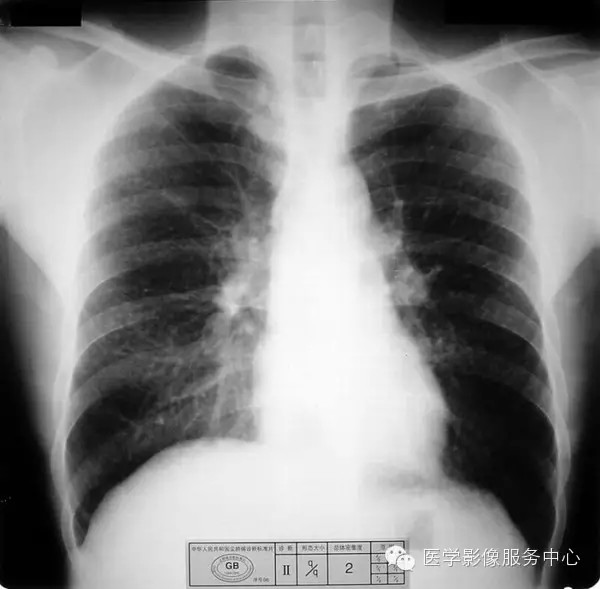

4.3 二期尘肺(Ⅱ)

a)Ⅱ:有总体密集度2级的小阴影,分布范围超过4个肺区;或有总体密集度3级的小阴影,分布范围达到四个肺区。

b)Ⅱ :有总体密集度3级的小阴影,分布范围超过4个肺区;或有小阴影聚集;或有大阴影,但尚不够诊断为Ⅲ者。